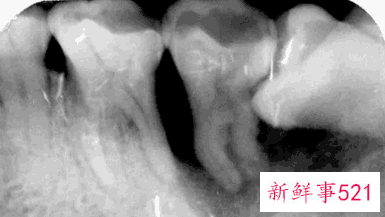

通常患者不自知,而由牙医以X光诊断得知。通常智齿萌发的空间不足,而会倒在第二大臼齿上,因而造成第二大臼齿清洁不易,甚至是牙齿部分吸收的现象,造成患者不舒适或牙疼。

3、智齿生长发育的空间不够会导致牙列不齐,有时会往第二磨牙牙根上靠拢侵犯邻牙,导致第二磨牙龋坏或者牙根吸收的情况。

智齿生长方向顶着前牙牙颈部或牙根,顶在牙颈部时第七颗牙会发生龋坏,智齿也会发生龋坏,因为没有生长空间还会推动牙齿变得牙列拥挤。

5、拔智齿的时候医生会建议拍片,智齿的多变性比较大,拍片虽说是辅助却是必不可少的,小到牙片大到曲面断层甚至是CT。

如果说我们拔一颗智齿我们所能看到的只有这颗牙表面这一层牙釉质,甚至有的时候我们根本看不到这颗智齿,它生长的方向,牙根弯曲程度,牙根数目,根尖是否有炎症等等,上颌我们更需要知道上颌窦与根尖的距离,下颌神经管与牙齿之间的距离,所以我们需要拍片来了解这颗牙的位置、难度,以及治疗方法。